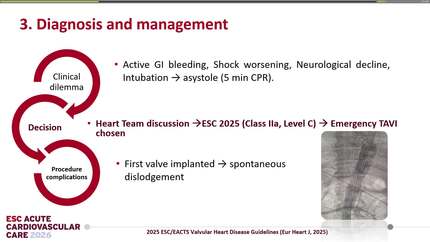

Rescue TTVR with a new-sized EVOQUE valve following transcatheter edge-to-edge repair